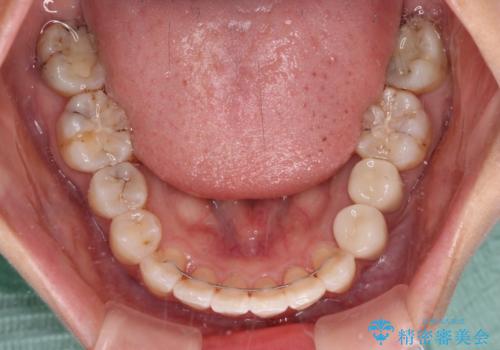

神経が取り除かれている歯は、クラウンによる補綴治療が必要であるため、矯正治療後にオールセラミッククラウンにて補綴治療を行うこととしました。

歯磨きしやすくなるとともに、飛び出していた前歯も引っ込めて整えることができました。